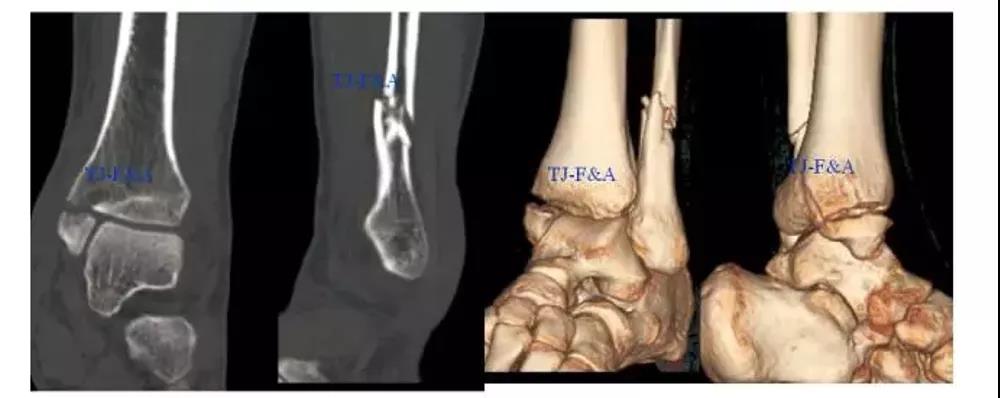

术前CT